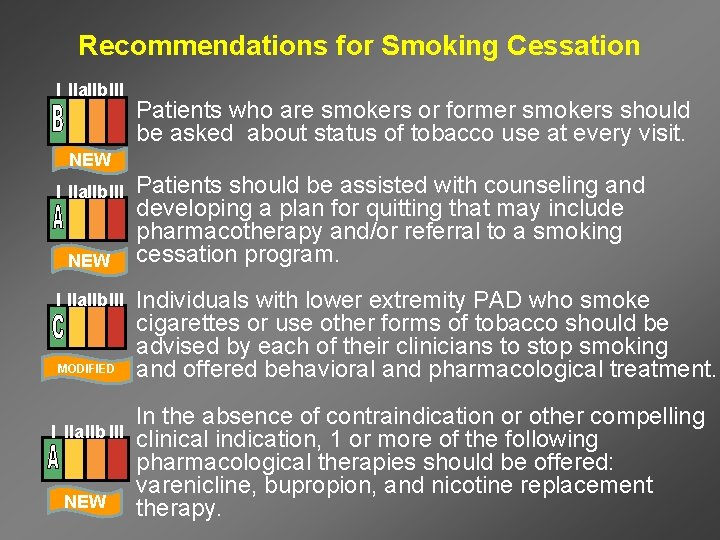

Recommendations for Smoking Cessation I IIa. IIb. III Patients who are smokers or former smokers should be asked about status of tobacco use at every visit. NEW I IIa. IIb. III MODIFIED I IIa. IIb III NEW Patients should be assisted with counseling and developing a plan for quitting that may include pharmacotherapy and/or referral to a smoking cessation program. Individuals with lower extremity PAD who smoke cigarettes or use other forms of tobacco should be advised by each of their clinicians to stop smoking and offered behavioral and pharmacological treatment. In the absence of contraindication or other compelling clinical indication, 1 or more of the following pharmacological therapies should be offered: varenicline, bupropion, and nicotine replacement therapy.